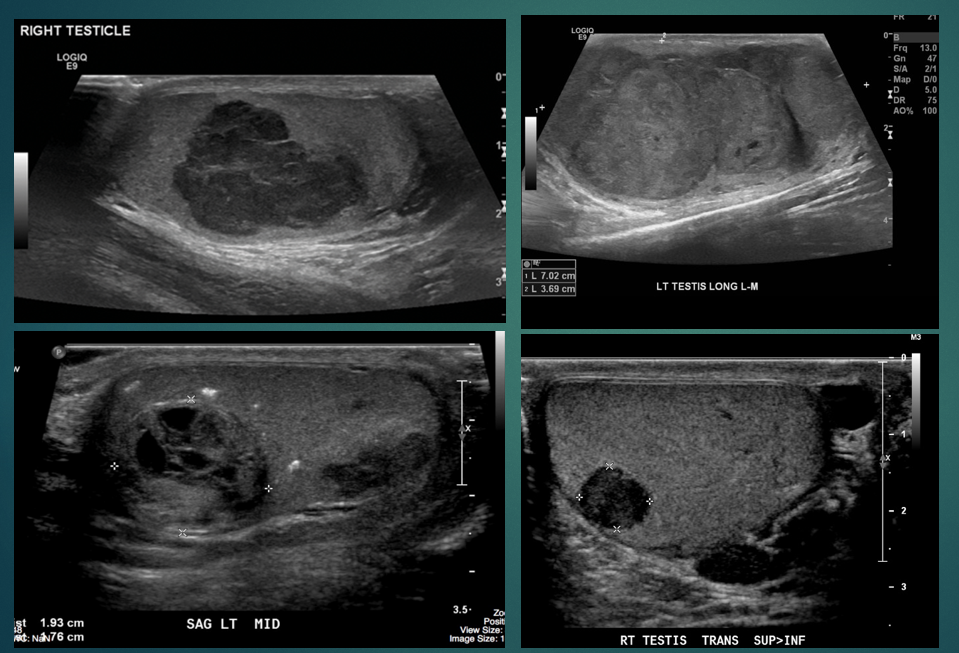

what does the image show

testicular tumour